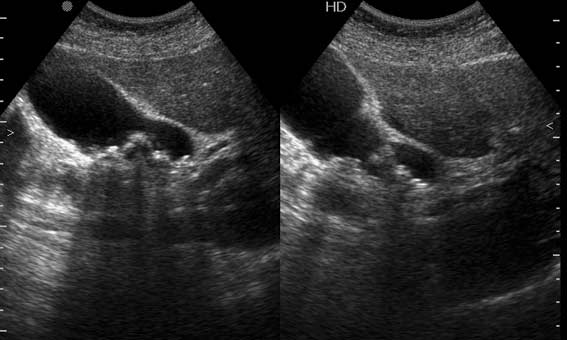

Мужчина 37 лет. Поступил в приемое отделение БСМП. Болен уже неделю, лечился в поликлинике. Сегодня боли усилились и стали нестерпимыми.

2 Между ж.пузырем и головкой панкреас -полый орган с отечными стенками-12 п.к.?(может быть сочетание язв.б-ни и ж.кам.б-ни)Если камень не в устье,то показана ФГС

Вы правильно разглядели пенетрирующую язву 12ПК. Перфорация прикрыта тканью печени, есть чуть-чуть свободной жидкости в ложе желчного пузыря. А ведь можно было "диагностировать" и острый холецистит!